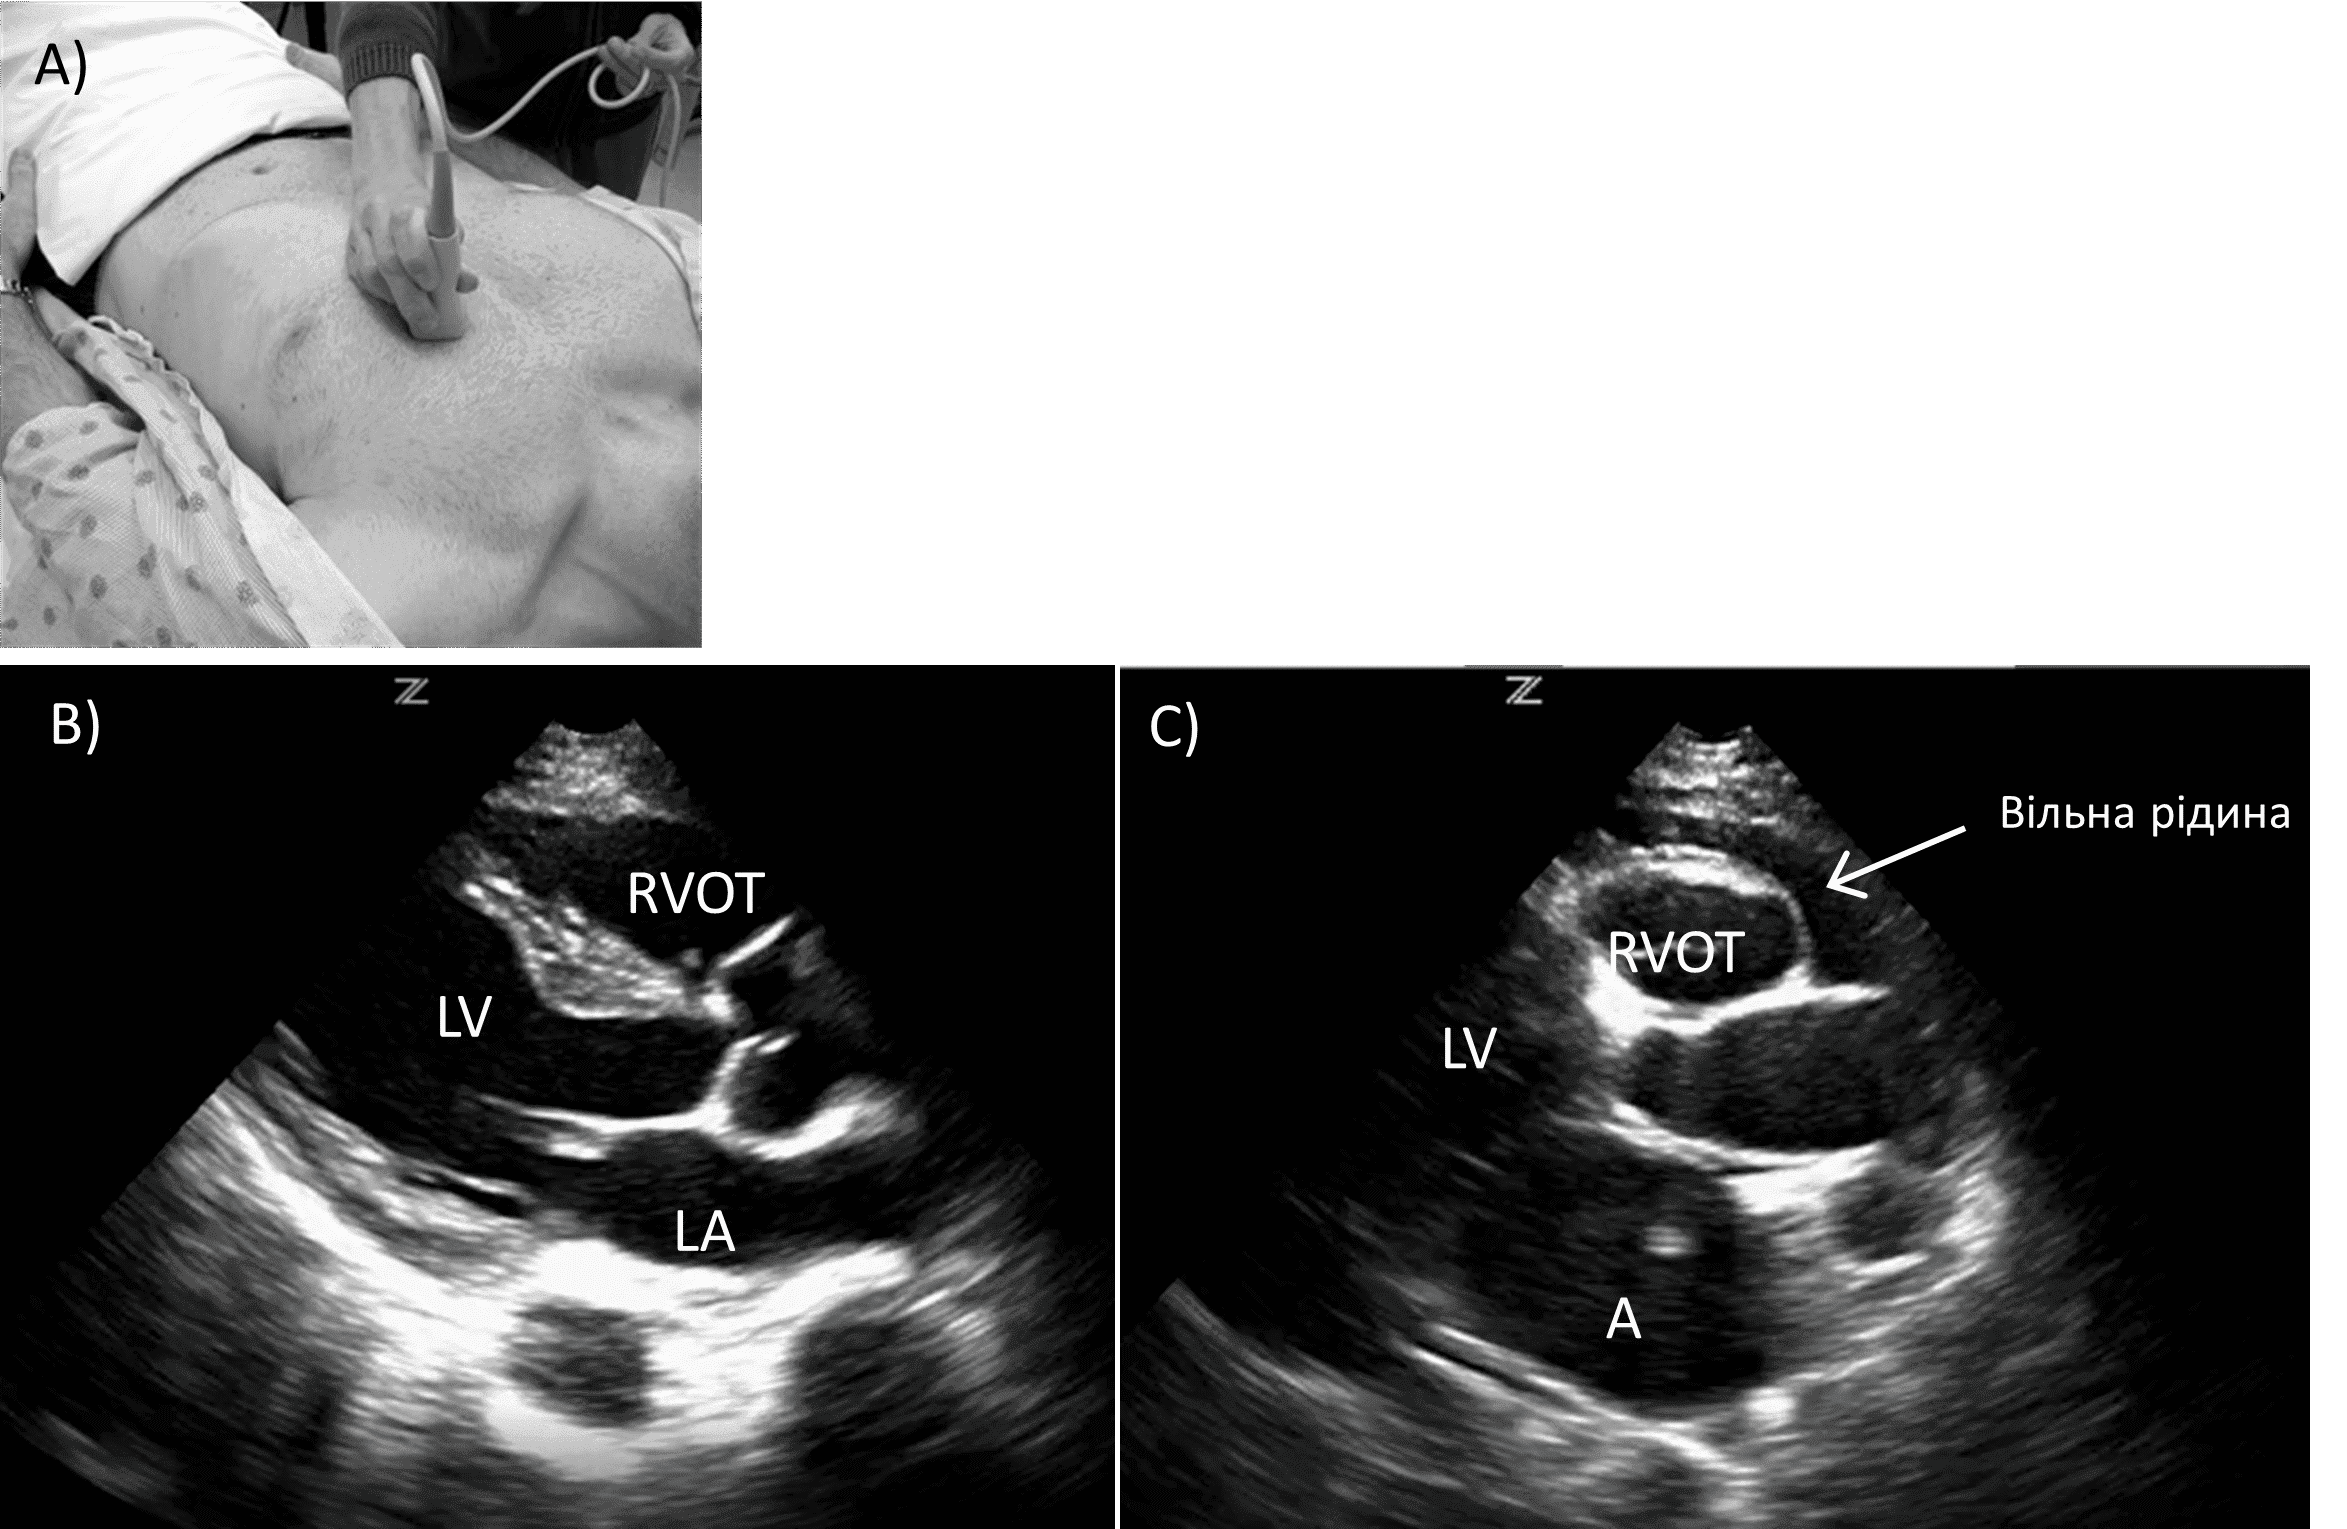

У пацієнтів з ожирінням або тих, хто не може переносити значний тиск на епігастральну ділянку, можна використовувати верхівковий чотирикамерний або парастернальний доступ по довгій осі. При парастернальному доступі датчик розташовують перпендикулярно в 4-му або 5-му міжребер’ї ліворуч від грудини, при цьому маркер датчика спрямовують на праве плече або ліве стегно пацієнта, залежно від уподобань лікаря. Це дозволяє візуалізувати правий шлуночок, міжшлуночкову перегородку, лівий шлуночок, ліве передсердя та низхідну аорту. Праве передсердя не візуалізується (зобр. 3).

Зобр. 3. Парастернальна позиція по довгій осі.

A) Розміщення датчика. B) Норма. C) Перикардіальний випіт. RVOT (вихідний тракт правого шлуночка), LA (ліве передсердя), LV (лівий шлуночок)